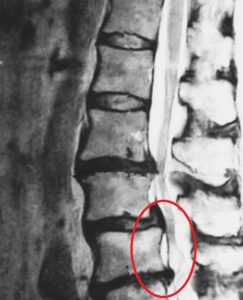

腰の骨(腰椎)は、積み木のように重なり合い、その間に「椎間板(ついかんばん)」というクッションがあります。

この椎間板の中には“髄核(ずいかく)”と呼ばれるゼリー状の物質があり、

衝撃を吸収する役割を果たしています。

ところが、姿勢の悪さや負担のかかる動作を繰り返すことで、

この椎間板が傷つき、髄核が外に飛び出して神経を圧迫してしまうことがあります。

この状態が「腰椎椎間板ヘルニア」です。